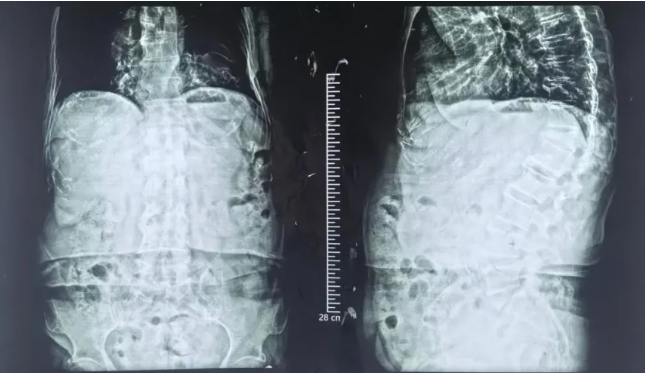

近日,一位80多岁高龄患者因胸12椎体骨质疏松性压缩性骨折,在我院骨科成功接受经皮椎骨成形术治疗。术后,患者椎体高度基本恢复,疼痛明显缓解,已能自由下地活动,恢复正常生活,重拾信心。

该患者因严重骨质疏松,导致胸12椎体明显压缩,长期饱受剧烈疼痛困扰,日常生活受到极大影响,身心备受煎熬。接诊后,骨科医疗团队经过详细检查和全面评估,结合其高龄、身体状况等因素,决定采用创伤小、恢复快的经皮椎骨成形术这一微创治疗方案,以帮助老人尽快摆脱病痛。

手术过程中,医生在影像引导下,通过微创穿刺将骨水泥精准注入受损椎体,成功稳定了骨折部位,使椎体高度基本恢复至正常水平。整个手术创伤小、时间短,安全性高,最大程度降低了高龄患者的手术风险。